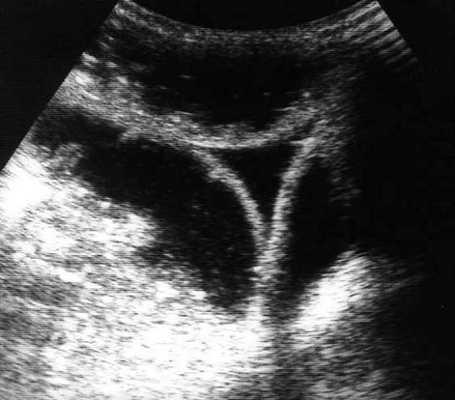

(а) При КТ с контрастированием в аксиальной проекции выявлена транспозиция верхней брыжеечной артерии (указатель) и вены (стрелка).

(б, в) На более низких уровнях при КТ в аксиальной проекции выявлен симптом «водоворота» (стрелка), представляющий собой перекручивание верхней брыжеечной вены и ее ветвей, брыжеечного жира и петель кишки вокруг верхней брыжеечной артерии по часовой стрелке.

Ультрасонография (УС) информативна при патологическом перекручивании верхних брыжеечных артерии и вены (симптом «водоворота»), выявляемом при цветном допплеровском картировании. Однако зависимость от мастерства исследователя, а также газ в тонкой кишке, мешающий исследованию верхних брыжеечных сосудов, часто ограничивают диагностическую пользу. КТ стала важным методом визуализационной диагностики, особенно при завороте тонкой кишки у взрослых. Как и при УС, характерным признаком при КТ служит симптом «водоворота», который возникает в результате перекручивания верхней брыжеечной вены и ее ветвей, брыжеечного жира, кишки и ветвей верхней брыжеечной артерии вокруг самой верхней брыжеечной артерии, чаще по часовой стрелке.